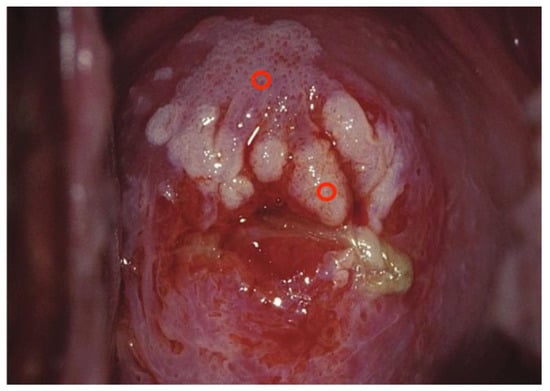

Images were deliberately identified when an objectively “difficult” colposcopic pattern was present. Nevertheless, the quality and resolution of all images, complete visibility of the entire cervix, absence of mucus/blood, and good representation of normal/abnormal colposcopic patterns were always identifiable; randomly selected images are illustrated as examples in Figure 1, Figure 2 and Figure 3.

Figure 2. Fully visible SCJ—G2—biopsy indicated.